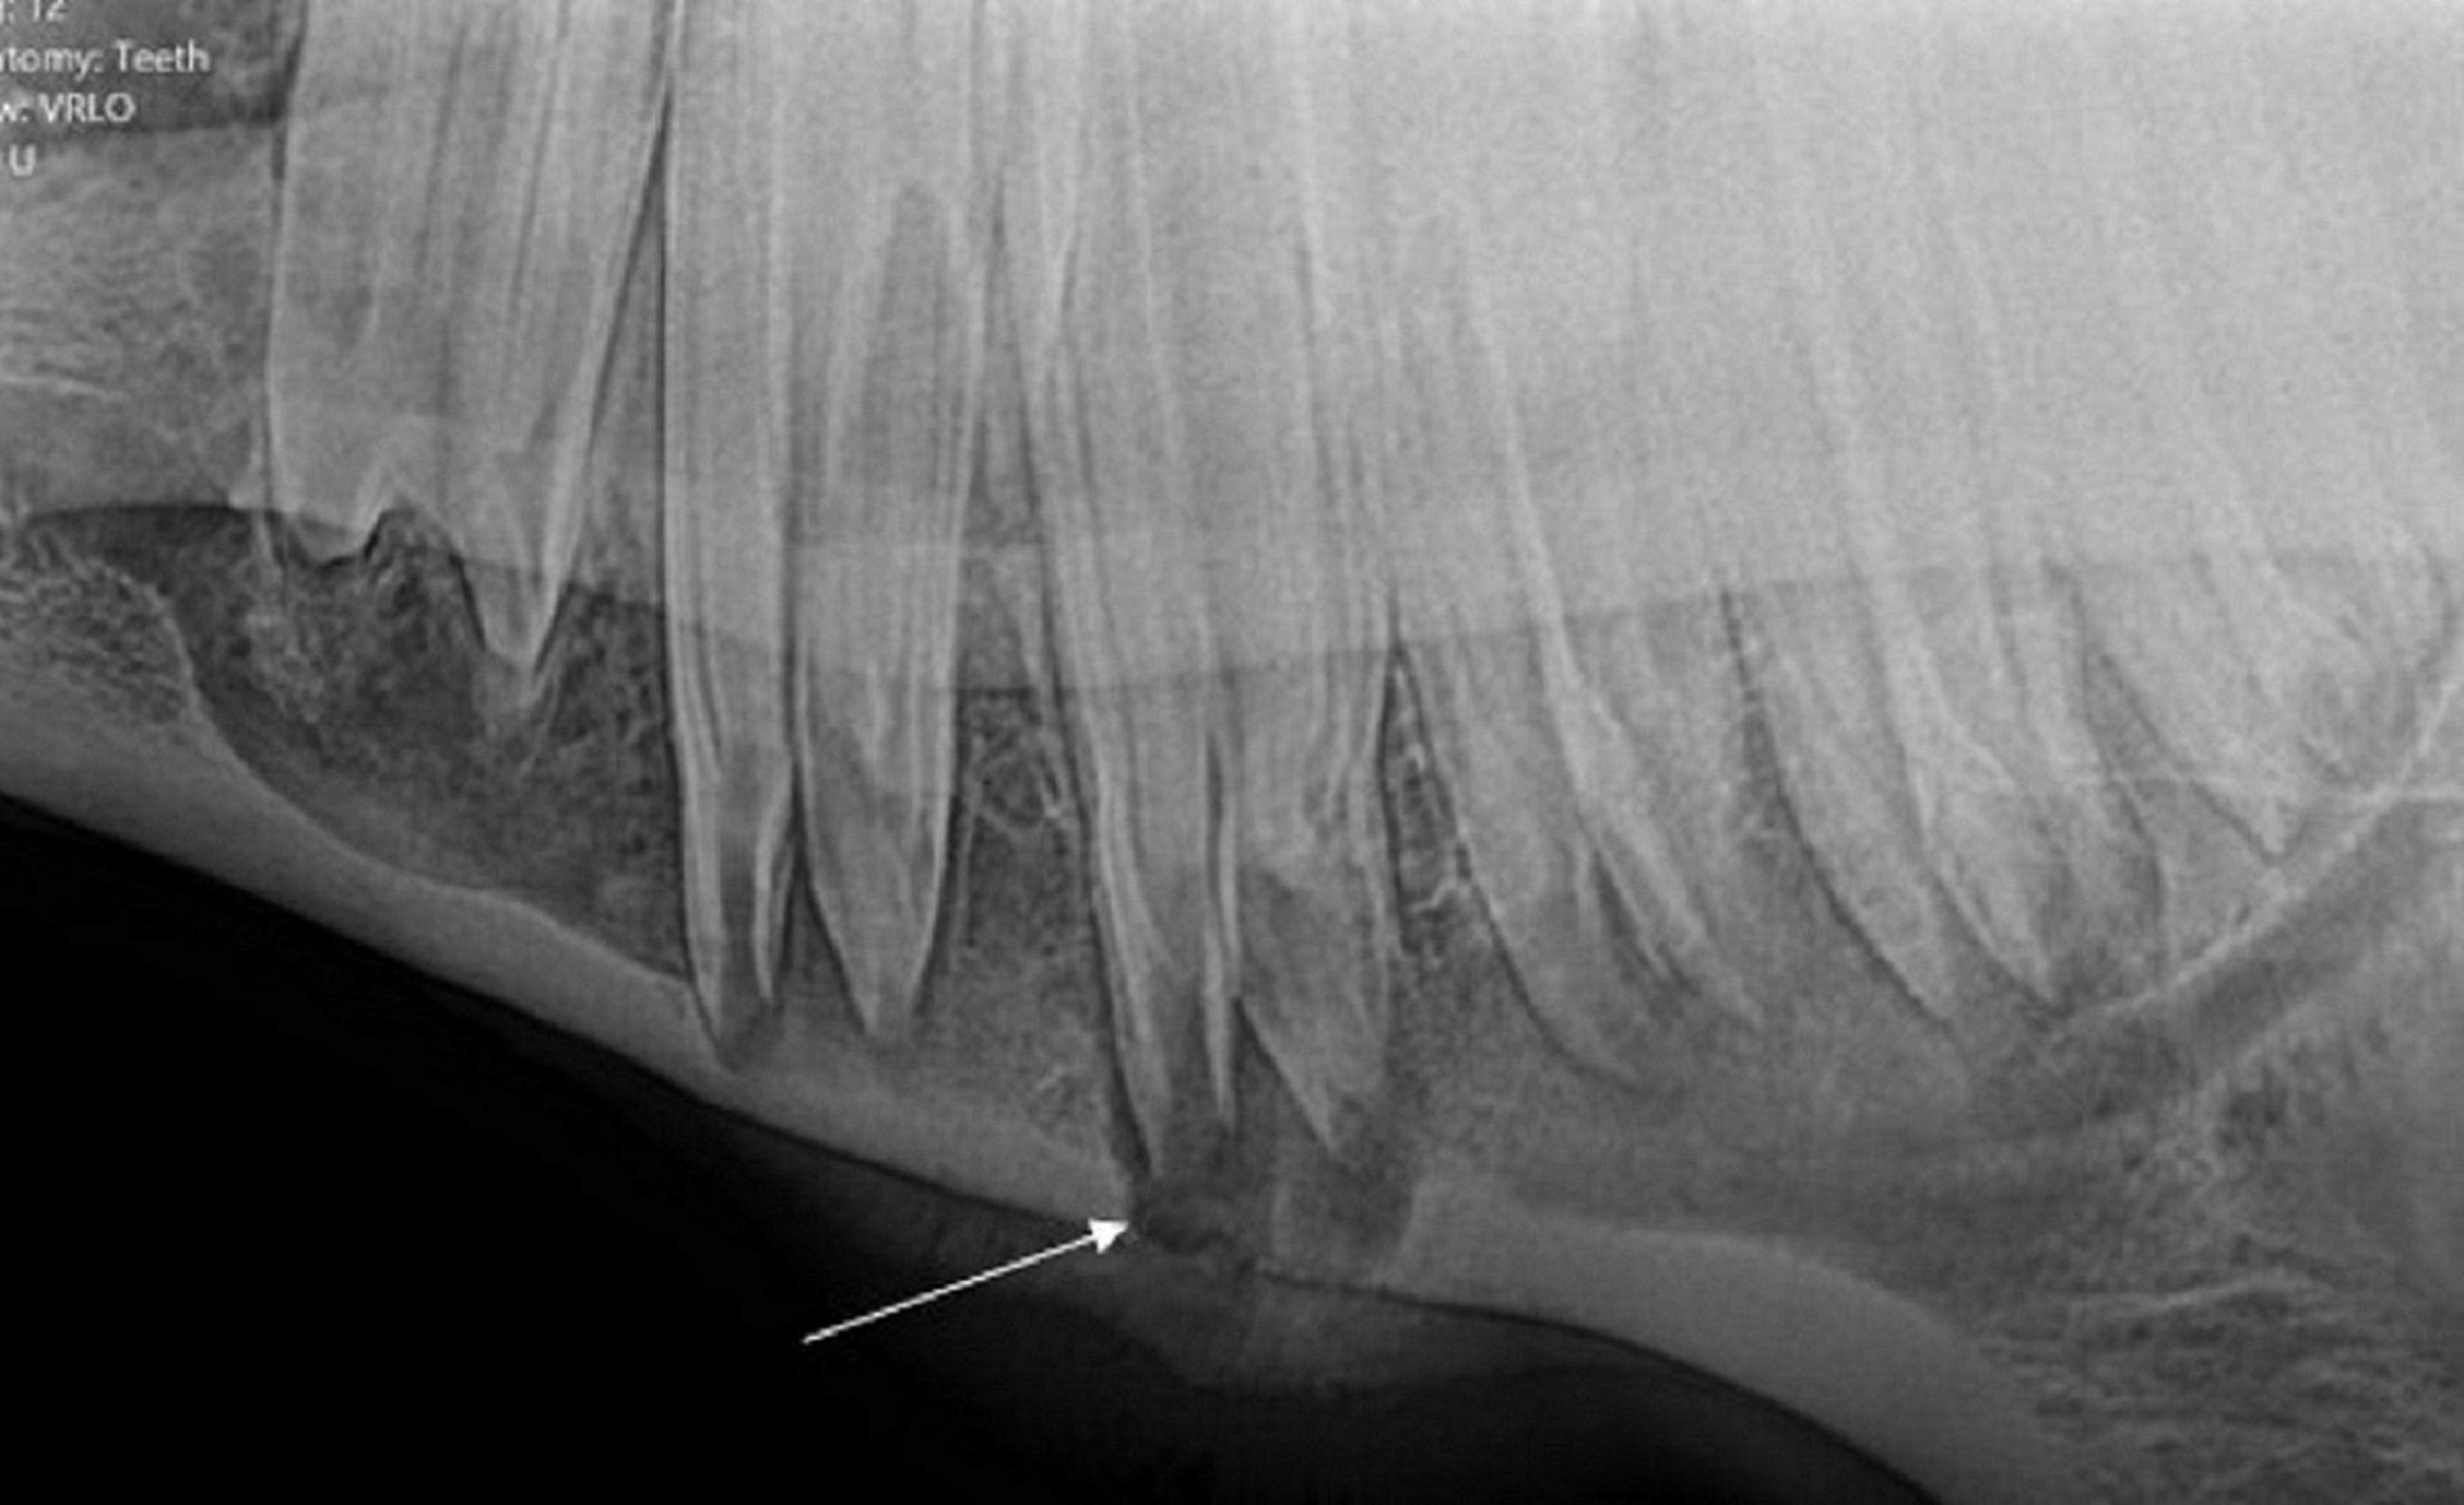

Osteítis apical (enfermedad endodóntica), caballo

Radiografía que muestra lisis apical y periapical en un caballo, con un tracto (flecha) desde el ápice radicular del cuarto premolar inferior. Alrededor del tracto hay osteítis y proliferación de hueso perióstico.

Cortesía del Dr. Jack Easley.